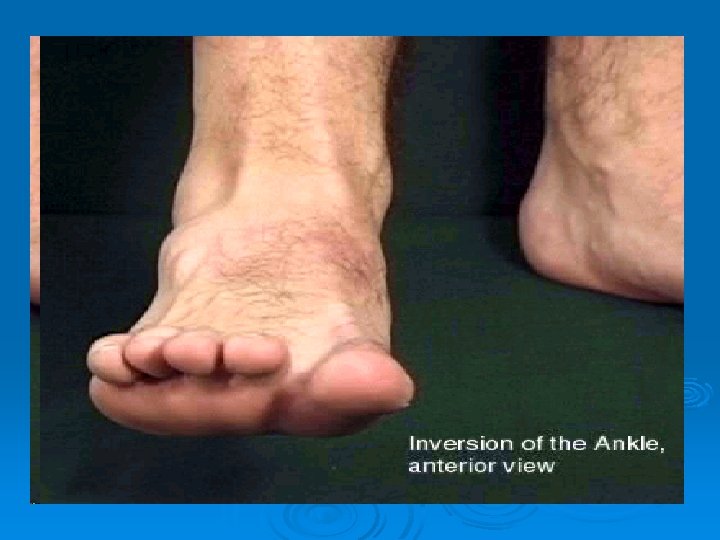

Lateral Ligaments of the Ankle Ø Resist ankle inversion Ø Anterior talofibular (ATF) l Most commonly sprained Calcaneofibular (CF) Ø Posterior talofibular (PTF) Ø

Ø 1 st Degree Ankle Sprain Ø Mechanism (MX) l Inversion and/or plantarflexion ATF most common sprained Ø Occurs during contact or non – contact. Ø